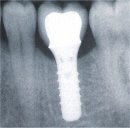

Erhalt des marginalen Knochenniveaus mit dem Astra Tech Implantat-System™

Die Standardnorm von 1986 hinsichtlich des Behandlungserfolges mit Zahnimplantaten spiegelt nicht mehr das wider, was heute erreicht werden kann. Es gibt keine Begründung dafür, warum Zahnarzt oder Patient einen Verlust des marginalen Knochens von bis zu 1,5 Milimeter - basierend auf einem vor 20 Jahren festgelegen Standard - akzeptieren sollten. In zahlreichen wissenschaftlichen Studien wurde nachgewiesen, dass der mittlere Rückgang des marginalen Knochenniveaus mit dem Astra Tech Implantat-Systems™ nach fünf Jahren nur 0,3 Milimeter beträgt.